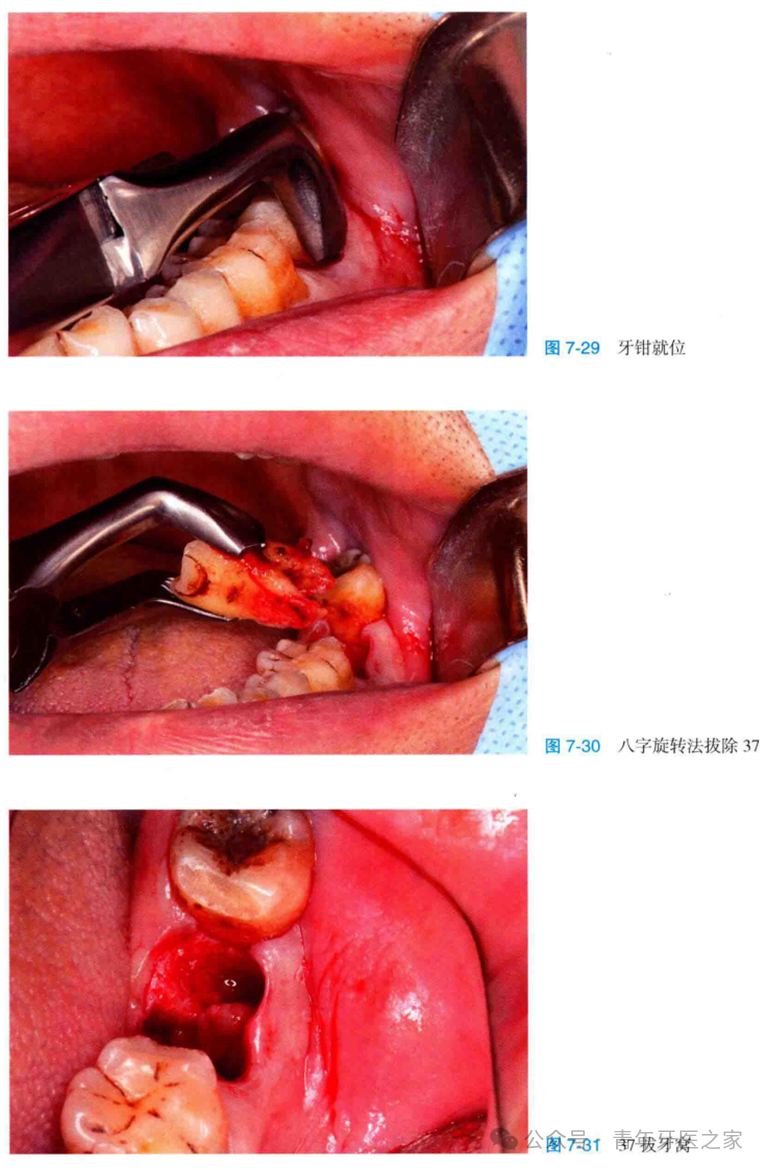

牙外伤及牙源性炎症是引起牙槽骨缺损或缺失最常见的口腔局部因素,如果缺损太多会影响后期的种植及美观。患牙拔除后同期行引导骨组织再生技术,是目前临床上最常见的保持牙槽高度和宽度的方法。

此类患牙由于牙槽骨的缺损拔除并不困难,但为了保证位点保存手术的成功率,拔除患牙后应彻底清理拔牙窝内的异物、炎性肉芽组织及死骨,并用生理盐水冲洗拔牙窝,直至可见拔牙窝骨壁且有新鲜血液从骨壁中渗出。